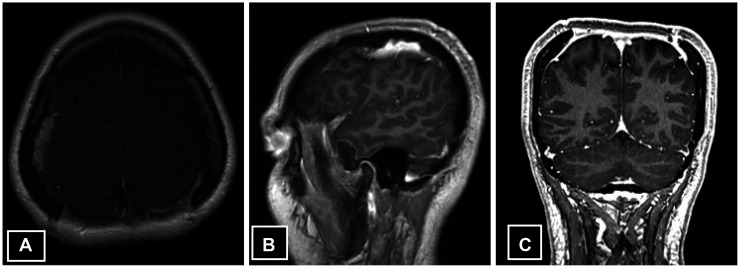

Langerhans cell histiocytosis (LCH) is a rare condition in adults, especially when it is limited to a single area of the skull, known as solitary calvarial involvement. In this case report, we present a unique instance of LCH affecting the parietal bone with a pus-draining fistula. This is a rare and unusual presentation at this location, which has been scarcely reported in medical literature. A 30-year-old woman with no prior comorbidity presented with complaints of headache that persisted for a year. She also had swelling on her scalp and a yellowish discharge for 3 weeks, but no neurological problems were observed. Radiology revealed thinning of the calvaria, with ragged margins along the inner table, multiple focal erosions, and involvement of overlying soft tissue and bony sequestrum. The patient underwent biparietal craniotomy and excision of the lesion. The histopathology report showed LCH. After 8 months of follow-up, there was no recurrence. The management of solitary calvarial involvement by LCH with masquerading presentation as a scalp infection can be achieved through complete excision of the lesions, resulting in a favorable outcome.